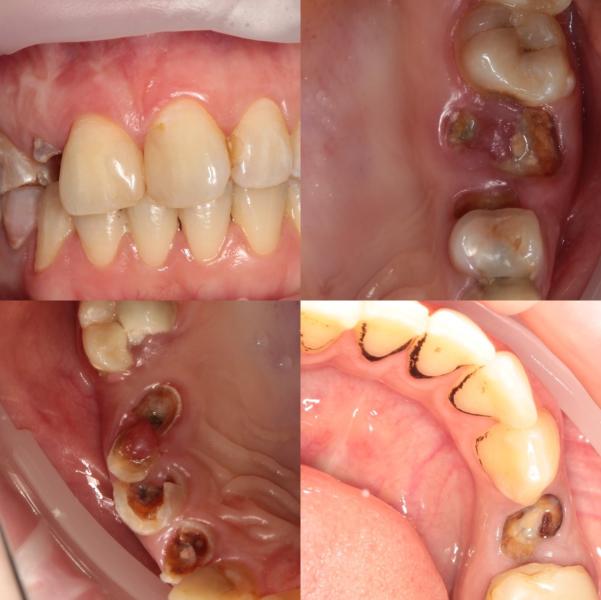

У пациентки 16 неделя беременности. Будем проводить комплексную чистку и удаление корешков , т.к имеются большие воспаления и плюс оставленные инфицированные корни - это дополнительный источник инфекции. После родов будем проводить комплексное лечение и устанавливать импланты